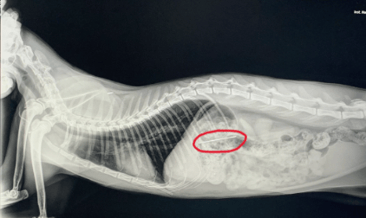

Thimble was rushed to the 24-hour vet, who confirmed with an Xray the needle was stuck in Thimble’s digestive tract and would require an emergency endoscopy under anesthesia to remove it (using a magnet!).